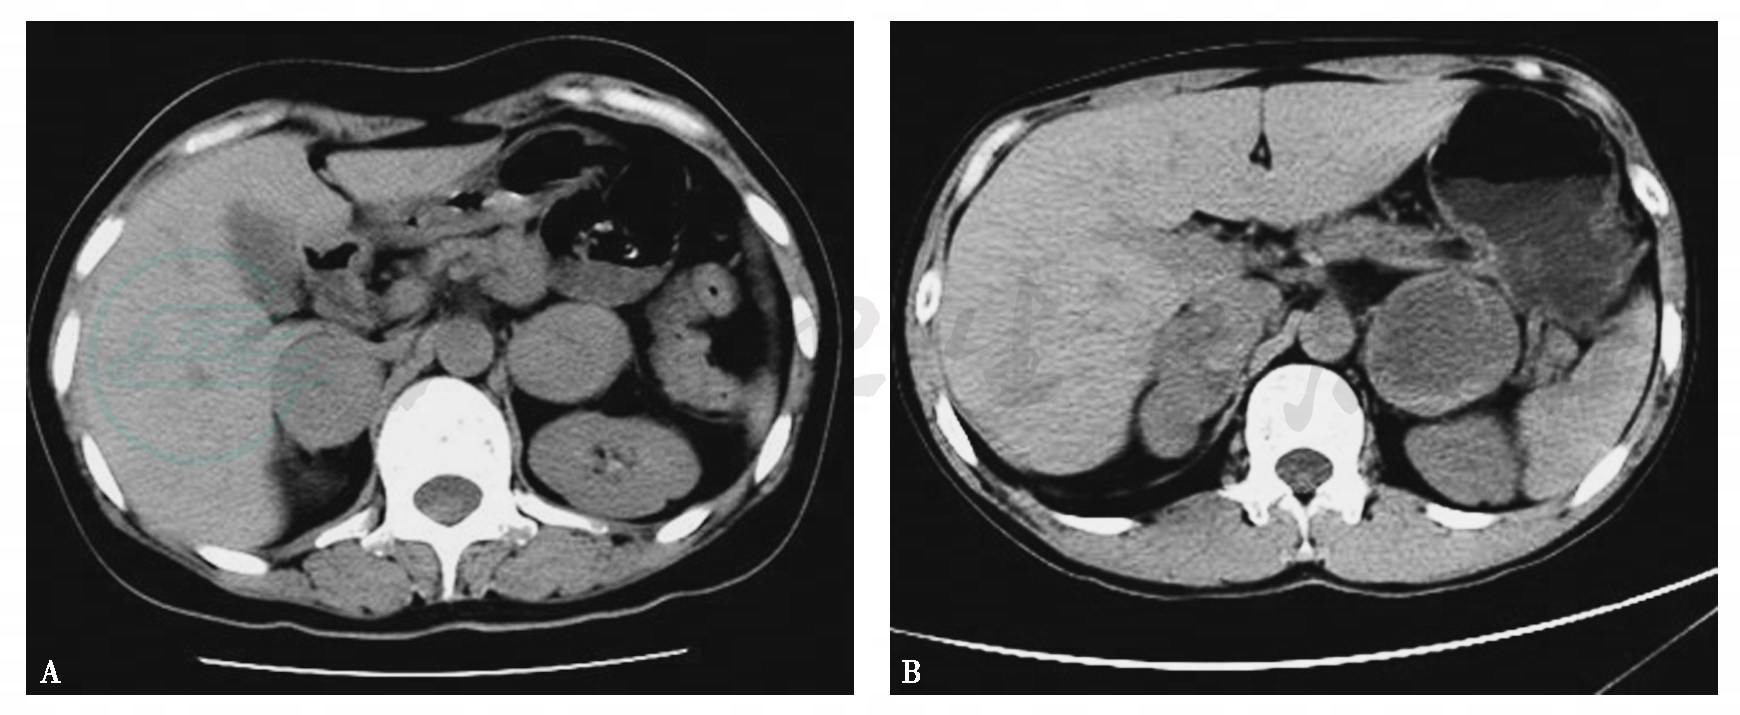

图3两侧肾上腺嗜铬细胞瘤

A.CT平扫示两侧肾上腺类圆形瘤体,密度尚均匀;B.CT平扫示两侧肾上腺瘤体,右侧瘤体不规则分叶状,左侧瘤体呈类圆形,其内囊变较明显